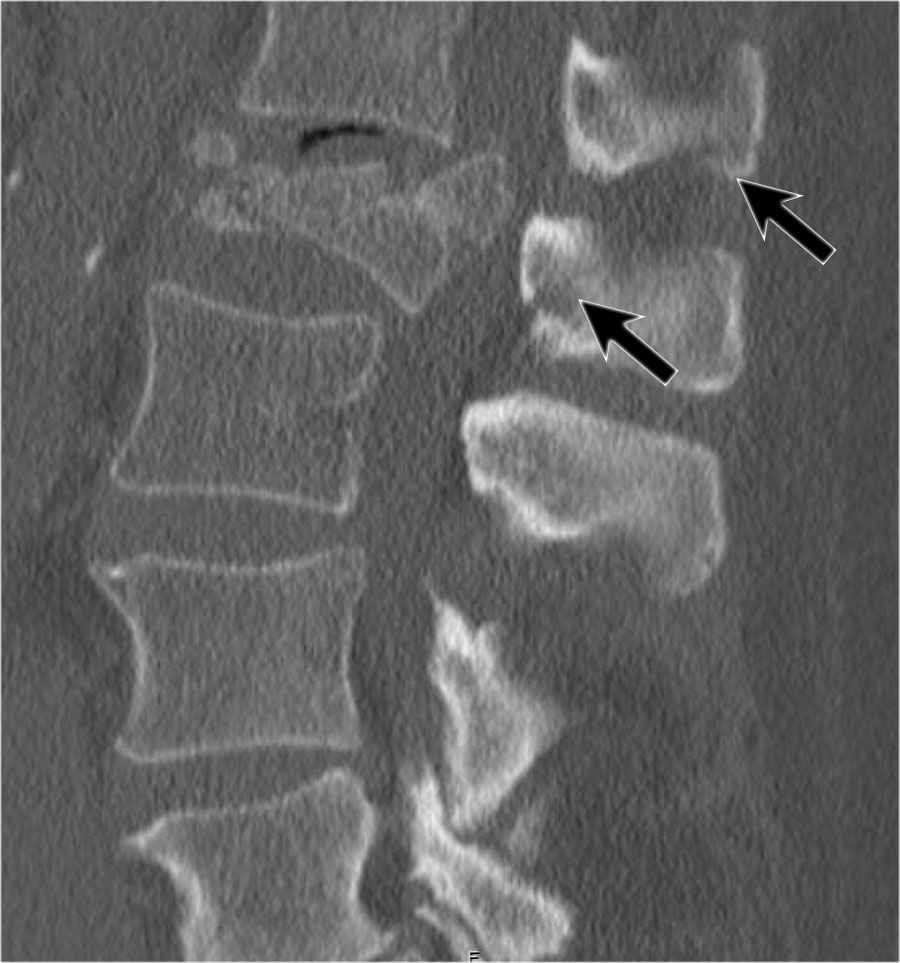

Mảnh xương góc sau trên thân đốt sống bị đẩy lùi ra sau (Retropulsion)

Hiện tượng mảnh xương bị đẩy lùi ra sau là đặc điểm điển hình của gãy vỡ, phân biệt rõ ràng với gãy nén đơn thuần.

Cuộn qua các hình ảnh.

Gãy theo mặt phẳng đứng dọc của thân đốt sống và

cung sau đốt sống

Gãy theo mặt phẳng đứng dọc của thân đốt sống và gãy cung sau theo mặt phẳng đứng dọc gặp lần lượt trong 90% và 85% các trường hợp gãy vỡ.

Dưới đây là bốn ví dụ minh họa.

Trong phân loại Denis, đây sẽ là gãy ba cột — trước/giữa/sau — cho thấy gãy xương rất không vững.

Tuy nhiên, trong phân loại TLICS, đây là gãy vỡ, tức là 2 điểm cho hình thái.

Phương pháp điều trị sẽ phụ thuộc vào tính toàn vẹn của PLC và tình trạng thần kinh.

Giãn rộng khoảng cách liên cuống (interpedicular distance)

Giãn rộng khoảng cách liên cuống, thường là hệ quả của đường gãy theo mặt phẳng đứng dọc, gặp trong 80% các trường hợp gãy vỡ.

Hình chiếu bên cho thấy các đặc điểm điển hình của gãy vỡ.